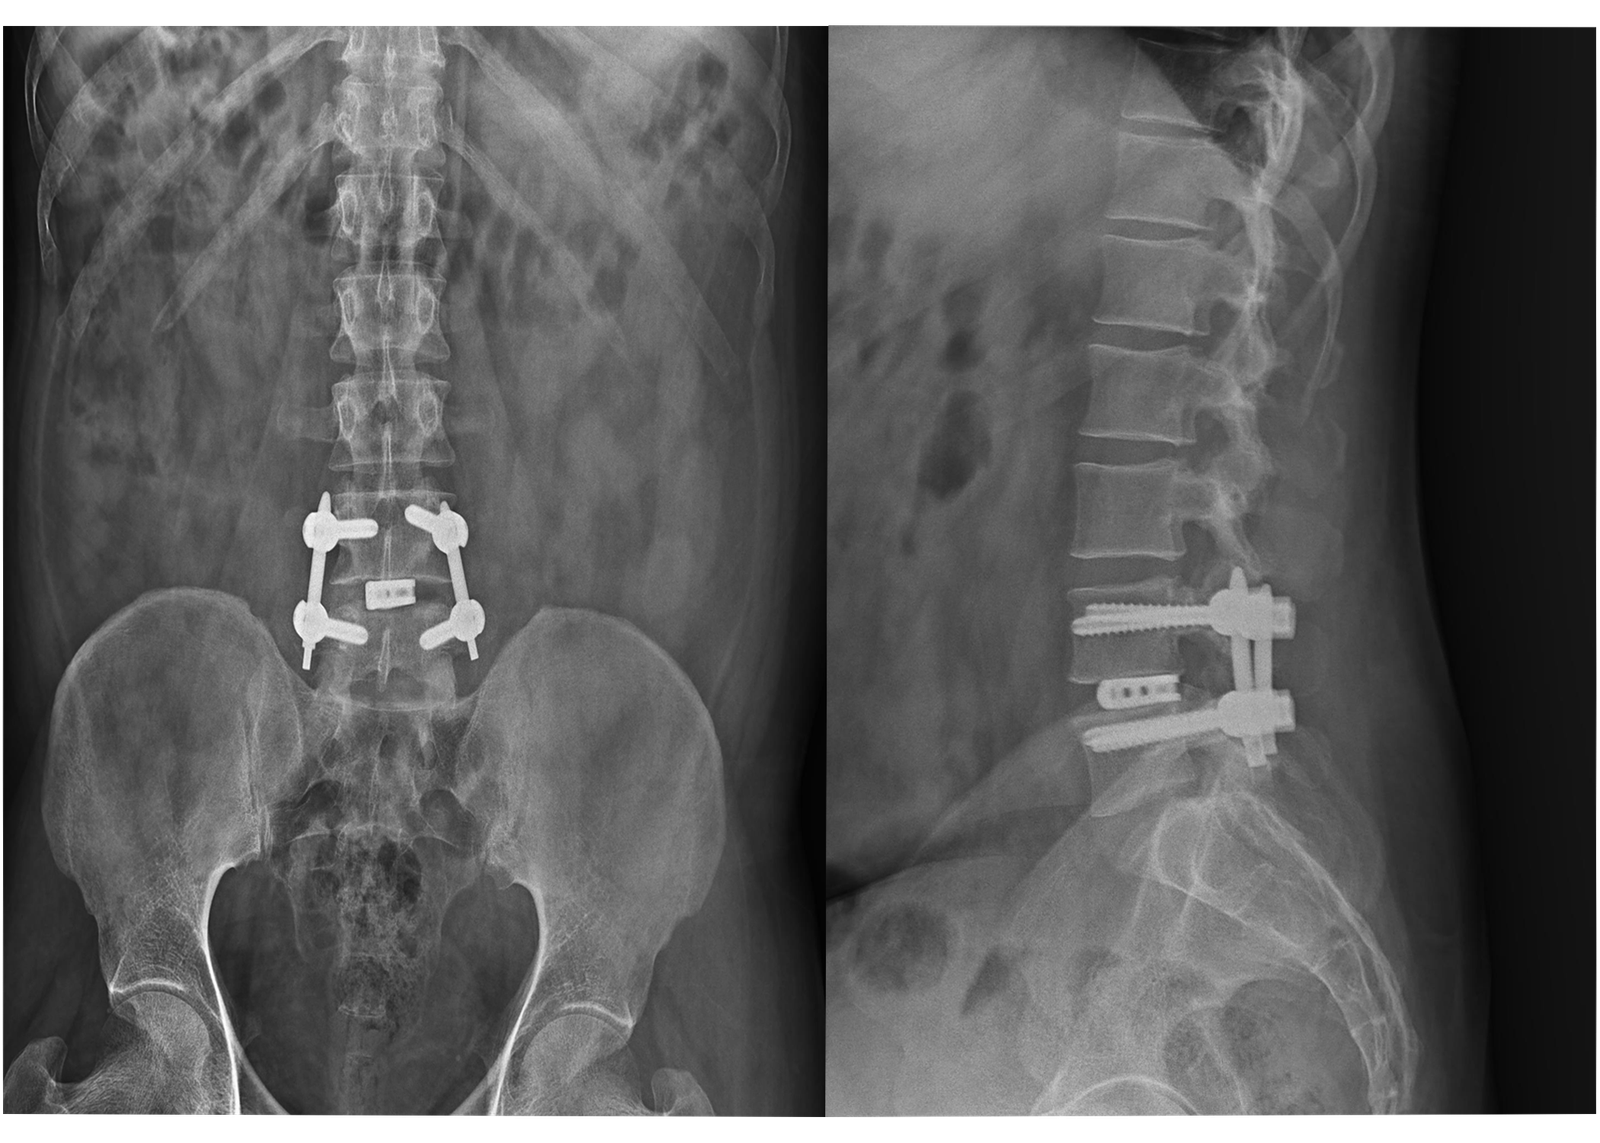

X-Rays